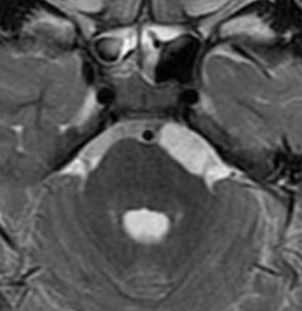

Ретроцеребеллярная киста головного мозга

Одной из распространенных патологий головного мозга считается киста. Это новообразование представляет собой пузырь, который наполнен жидкостью. В зависимости от месторасположения и его характера, выделяют несколько разновидностей патологий. Самыми распространенными считаются ретроцеребеллярная и арахноидальная. Первая из них может образоваться в любых отделах мозга. В отличие от других видов, ретроцеребеллярная киста появляется внутри органа по причине гибели клеток серого вещества. Арахноидальное новообразование же обычно возникает во внешних слоях головного мозга и заполнено спинномозговой жидкостью.

Причины ретроцеребеллярной арахноидальной кисты

Ученые, занимающиеся изучением данной патологии, пришли к мнению, что новообразование появляется в том месте, в котором случилась гибель клеток серого вещества. Этот процесс могут спровоцировать различные факторы. К наиболее распространенным относятся такие:

После опроса специалист назначит аппаратные методы диагностики, поскольку выявить без них кисту головного мозга не представляется возможным. К самым информативным способам относятся КТ и МРТ. Они с высокой точностью покажут размеры и локализацию новообразования.

Лечение ретроцеребеллярной кисты головного мозга

После того как диагноз будет подтвержден, можно приступать к устранению симптомов и причин. В некоторых случаях, когда киста головного мозга увеличивается не слишком стремительно, может быть назначено консервативное лечение. Оно ориентировано на борьбу с инфекционными или воспалительными процессами, которые спровоцировали рост новообразования. Если есть прямые показания и врач считает необходимостью, то проводится оперативное вмешательство. Самыми современными и эффективными считаются: